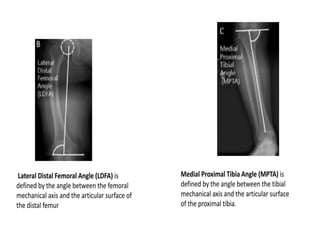

DRENNAN ANGLE

IMAGING

Radiographs

• standing long-cassette AP radiograph of both lower

extremities

• ensure that patella are facing forwards for evaluation

(commonly associated with internal tibial torsion)

– findings suggestive of Blounts disease

• medial and posterior sloping of proximal tibial

epiphysis(short ,thin,wedged,irregular)

• varus focused at proximal tibia

• severe deformity(asymmetric bowing)

• sharp angular deformity(progressive)